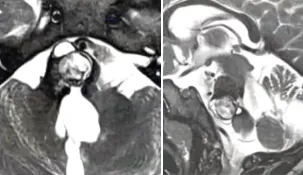

孕期发现脑干海绵状血管瘤,还能保母子平安吗?

怀孕期间发现患有脑海绵状血管瘤是比较罕见的情况,但一旦发生就会很棘手了。INC国际神经外科专家巴特朗菲(Helmut Bertalanffy)教授团队在相关研究中就对高功能区脑干海绵状血管瘤孕妇的处...